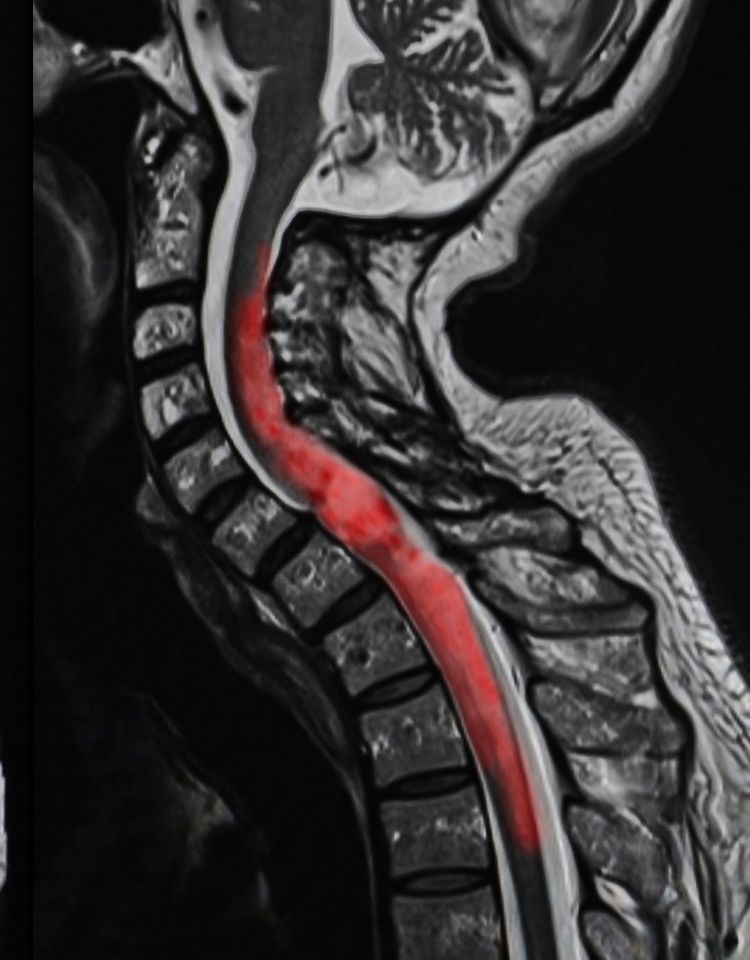

The National Institute of Neurological Disorders and Stroke describes SCIs as “damage to the bundle of nerves and nerve fibers that sends and receives signals from the brain” extending from the “lower part of the brain down through the lower back”. This injury can be caused by trauma directly to the spinal cord itself or indirectly through trauma to the tissue or vertebrae surrounding the spinal cord. The severity of an SCI depends on both the extent and location of the injury.

An SCI can be complete or incomplete. A complete SCI causes permanent damage to the spinal cord causing paraplegia or quadriplegia[1]. An incomplete SCI occurs when the damage to the spinal cord is partial and will affect the amount of feeling and movement to a varying degree.

• Cervical spinal cord injuries: These are often the most severe level of SCI; they include the seven vertebrae (C-1 to C-7) in the neck. Because these vertebrae are closer to the brain and affect a larger portion of the body, these injuries typically result in quadriplegia, causing limited or absent feeling or movement below the shoulders and neck.

• Thoracic spinal cord injuries: The thoracic spine includes twelve vertebrae located in the thoracic spine, which affects muscles in the upper chest, mid-back, and the abdominal muscles. An injury to the thoracic spine can lead to pain that radiates into the arms, legs, and around the rib cage.

• Lumbar spinal cord injuries: The lumbar spine is the lowest part of the spine and carries the most weight of all the sections. An injury to the five lumbar vertebrae will generally result in some loss of function of the lower body but not the upper.